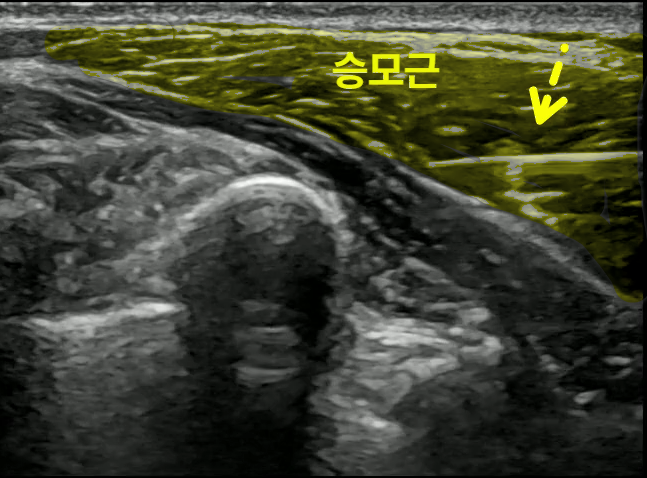

@ Atlas app. > 견정혈 (肩井, GB21)

제가 출판한 전공 서적의 '견정혈'의 초음파 영상입니다. 견정혈은 ## 승모근 통증, 어깨 담 결림을효과적으로 치료하는 혈자리*로

"도침"**과 같은 특수침으로

섬유화된 근막을 떼어내어

만성통증을 해결**할 수 있습니다.

초음파 가이드 침도 시술

경혈초음파로 견정혈을 확인하여

초음파 유도하 도침 시술하는 모습입니다.

견정혈에서 정확한 깊이로

승모근을 치료하면 아주 만족도가 높습니다.